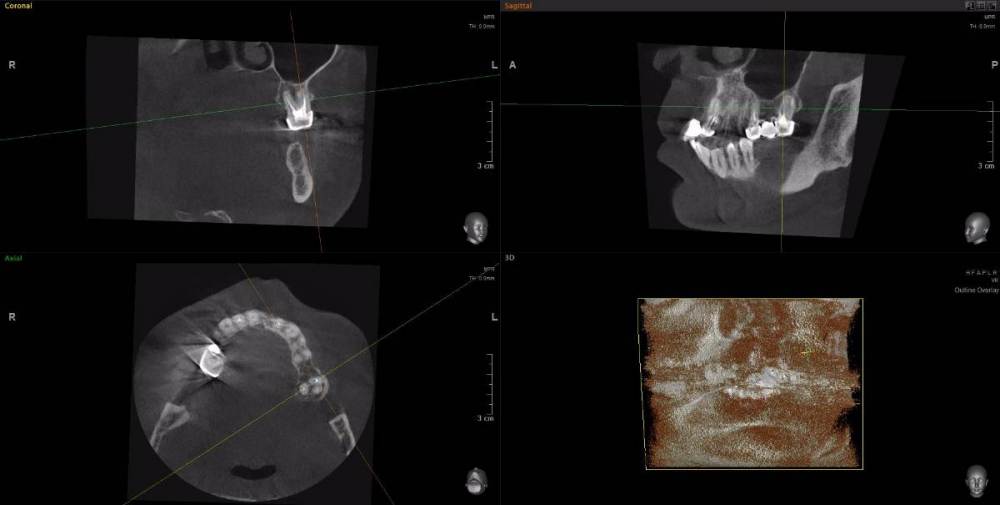

Dude Опубликовано 1 апреля, 2021 Автор Поделиться Опубликовано 1 апреля, 2021 https://disk.yandex.ru/d/6d0pmZ1zArn1Og Так? Ссылка на комментарий